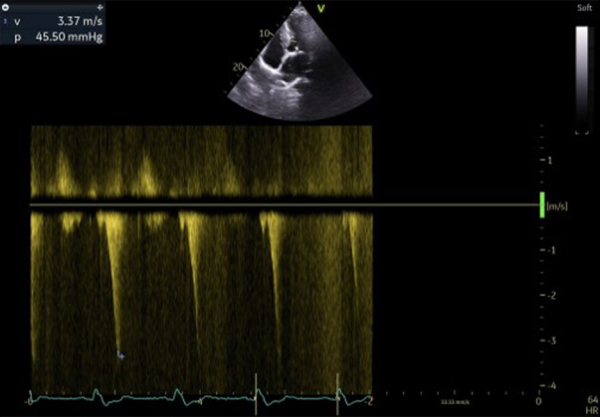

Le septum inter ventriculaire est mesuré à 18mm contre 21 mm avant initiation du traitement et le gradient max en doppler continu trans-aortique au Valsalva a diminué de 68 mm Hg à 45 mm Hg.

Echocardiographie

Figure 6 : flux Doppler continu trans-aortique